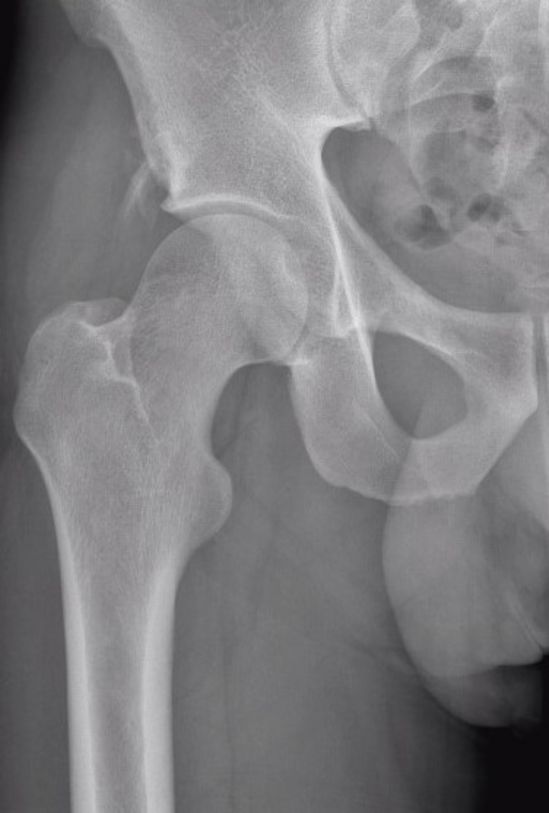

Rectus femoris-Verletzungen werden anhand einer klinischen Untersuchung und mit Hilfe von Röntgenbildern diagnostiziert. Dabei fallen oft ein Hämatom (Bluterguss) und Schmerzen am anterioren (vorderen) Beckenbereich (Spina iliaca anterior superior) und in der Leiste auf. Die Kraft bei der Kniebeugung kann reduziert sein und die Bewegung löst typischerweise Schmerzen aus. Im Röntgenbild könnte ein knöcherner Ausriss ersichtlich sein. Eine MRI-Untersuchung ist für die Diagnose nicht entscheidend, kann aber bei schweren Symptomen wichtige Informationen über das Verletzungsausmass geben (Retraktion, Grösse der Ruptur).

Links ein Röntgenbild und rechts eine MRI-Aufnahme der rechten Hüfte mit knöchernem Ausriss des proximalen Musculus rectus femoris.

Bilder: Universitätsklinik Balgrist